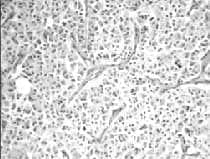

Figura 4. Patología microscópica de tumor carcinoide endobronquial

Cortesía Dra. Paulina Ojeda, Patóloga Hospital Santa Clara E.S.E.

Figura 7. Patología microscópica tumor carcinoide bronquial atípico.

Cortesía Dra. Paulina Ojeda, Patóloga, Hospital Santa Clara E.S.E.

Figura 8. Patología microscópica de tumor carcinoide bronquial.

Cortesía Dr. Carlos Garavito, Cirujano de Tórax; Hospital Santa Clara E.S.E.